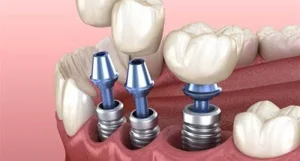

Today, replacing missing teeth with dental implants is considered the standard treatment for single-tooth spaces. Numerous clinical studies have shown that single-tooth implant treatment is